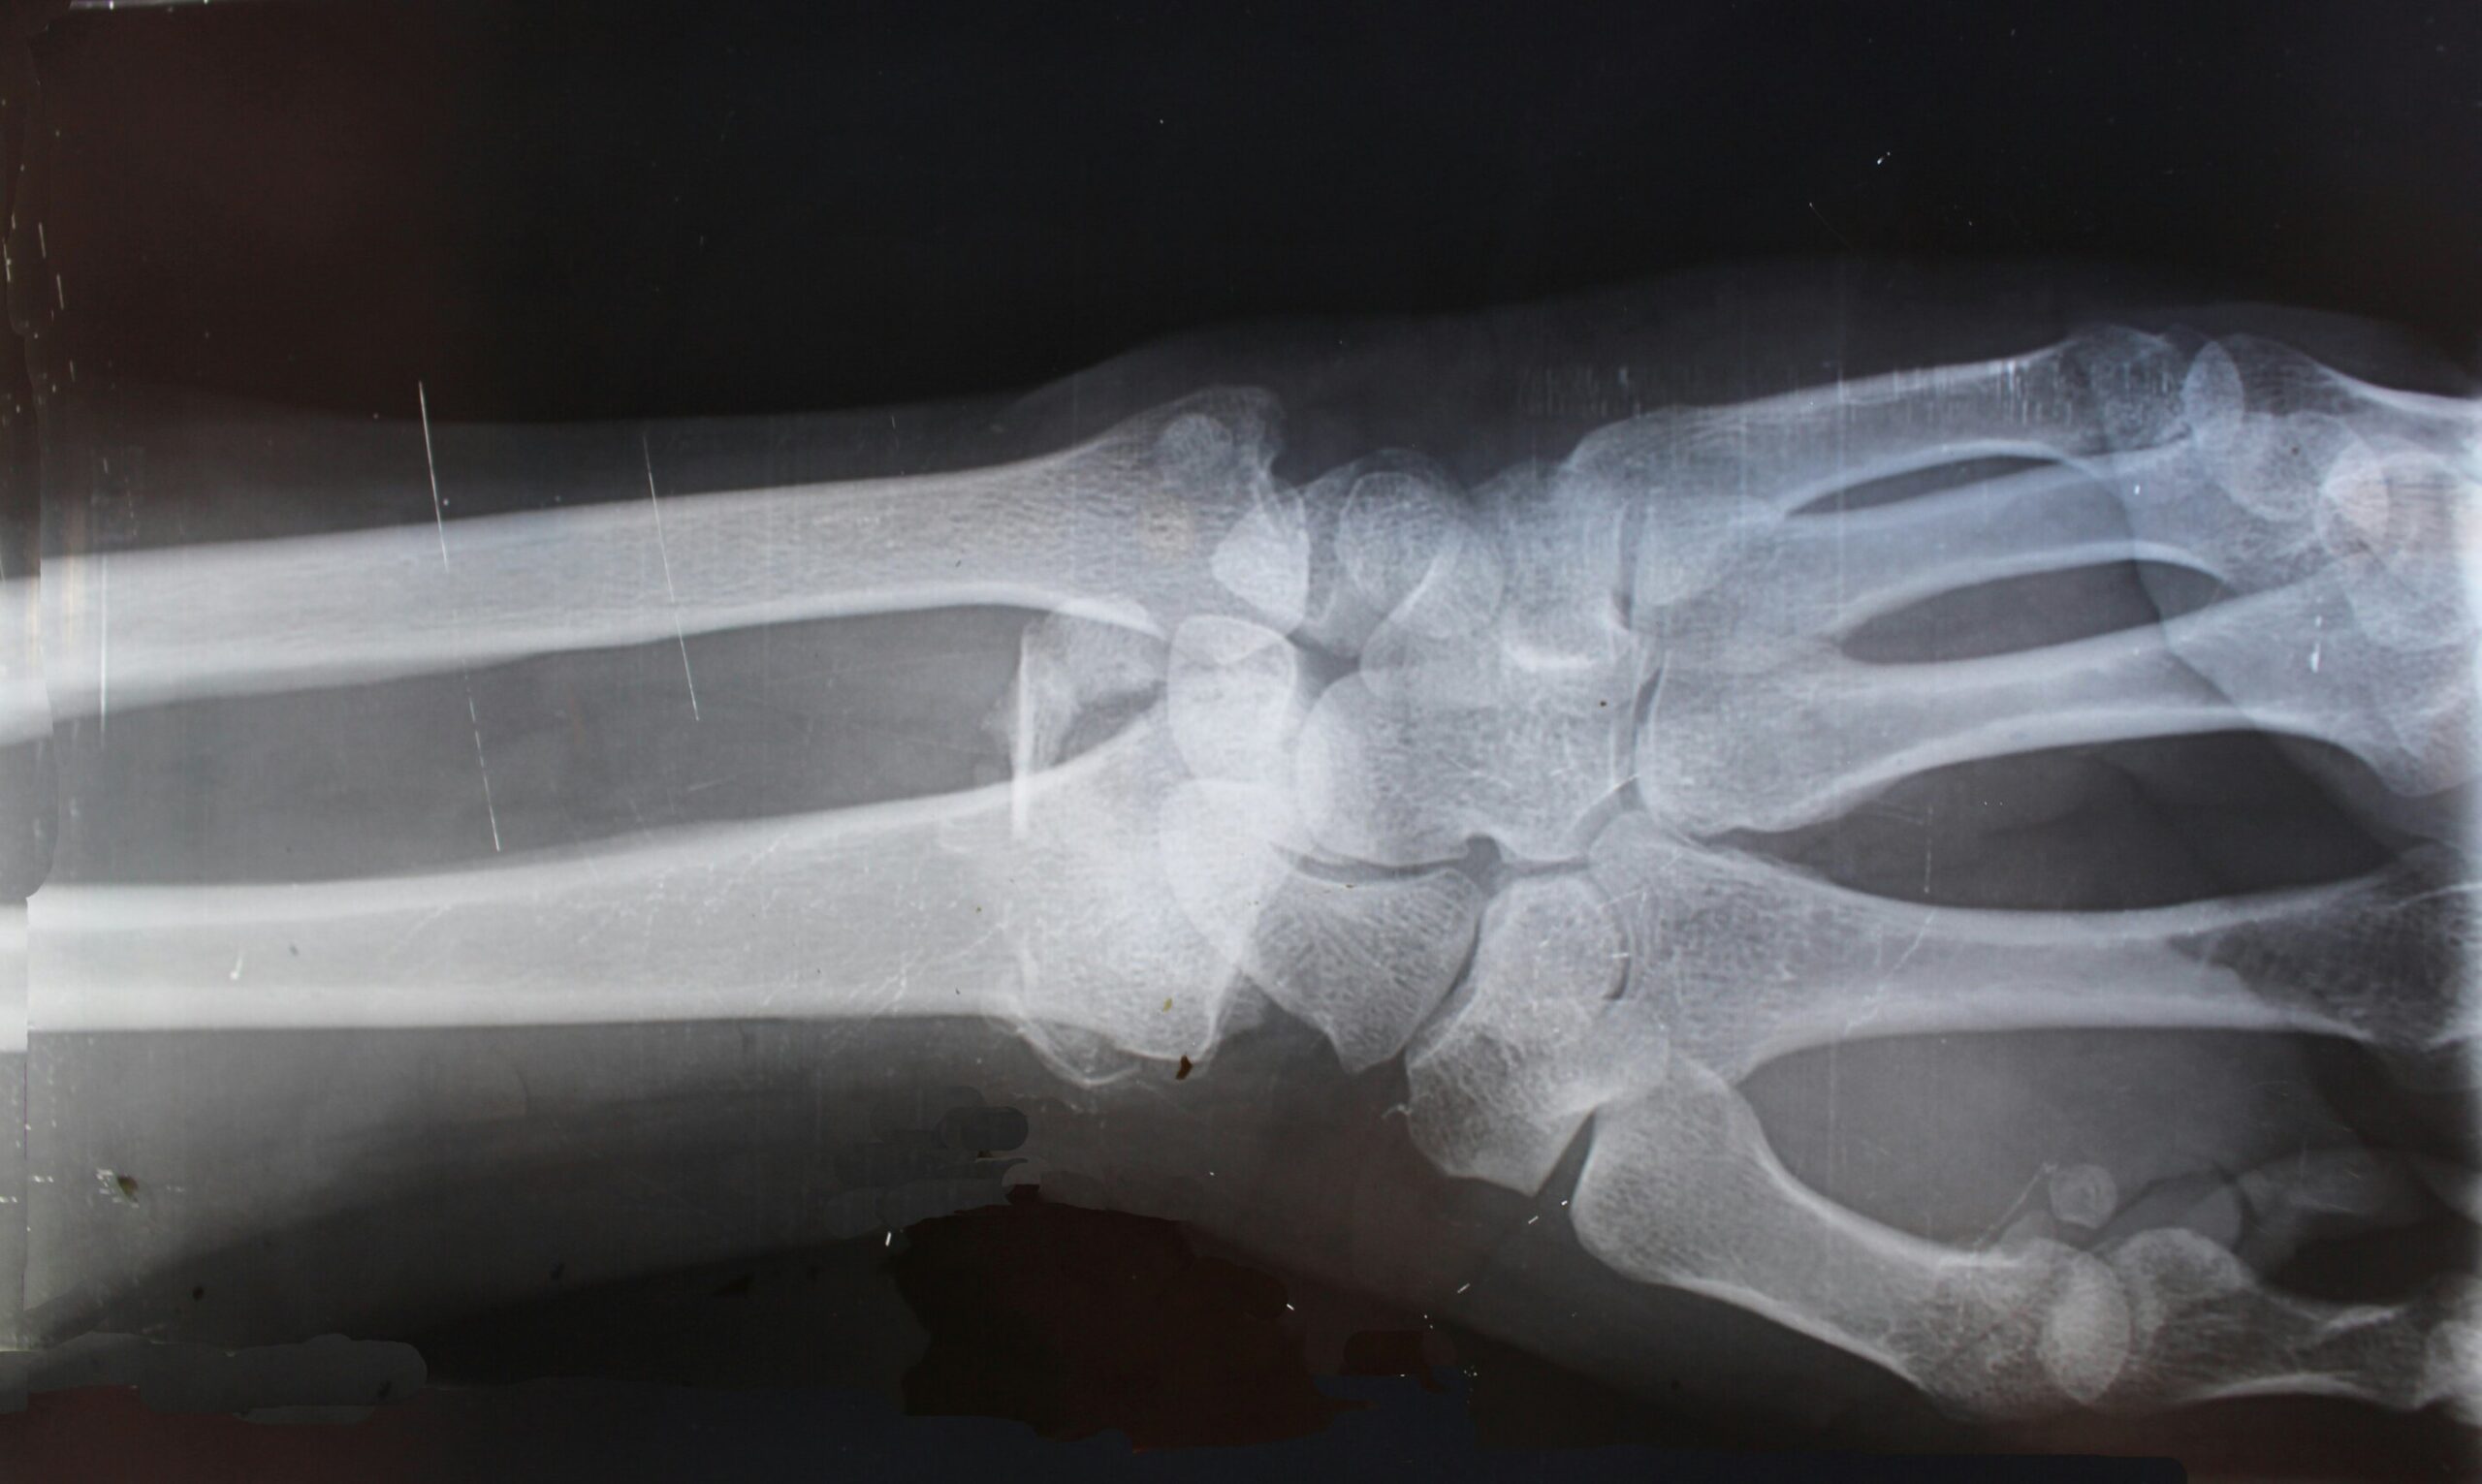

L’ostéosarcome est le type de cancer des os le plus courant et se développe généralement dans les bras ou les jambes. Les symptômes peuvent inclure des douleurs osseuses, une grosseur ou un gonflement et un os qui se brise facilement. Les experts estiment que moins de 1 000 personnes aux États-Unis développent un ostéosarcome chaque année. Environ 7 personnes sur 10 survivent si la maladie ne se propage pas à d’autres parties du corps, mais seulement 2 enfants sur 10 survivent si la maladie se propage en dehors du site osseux d’origine.